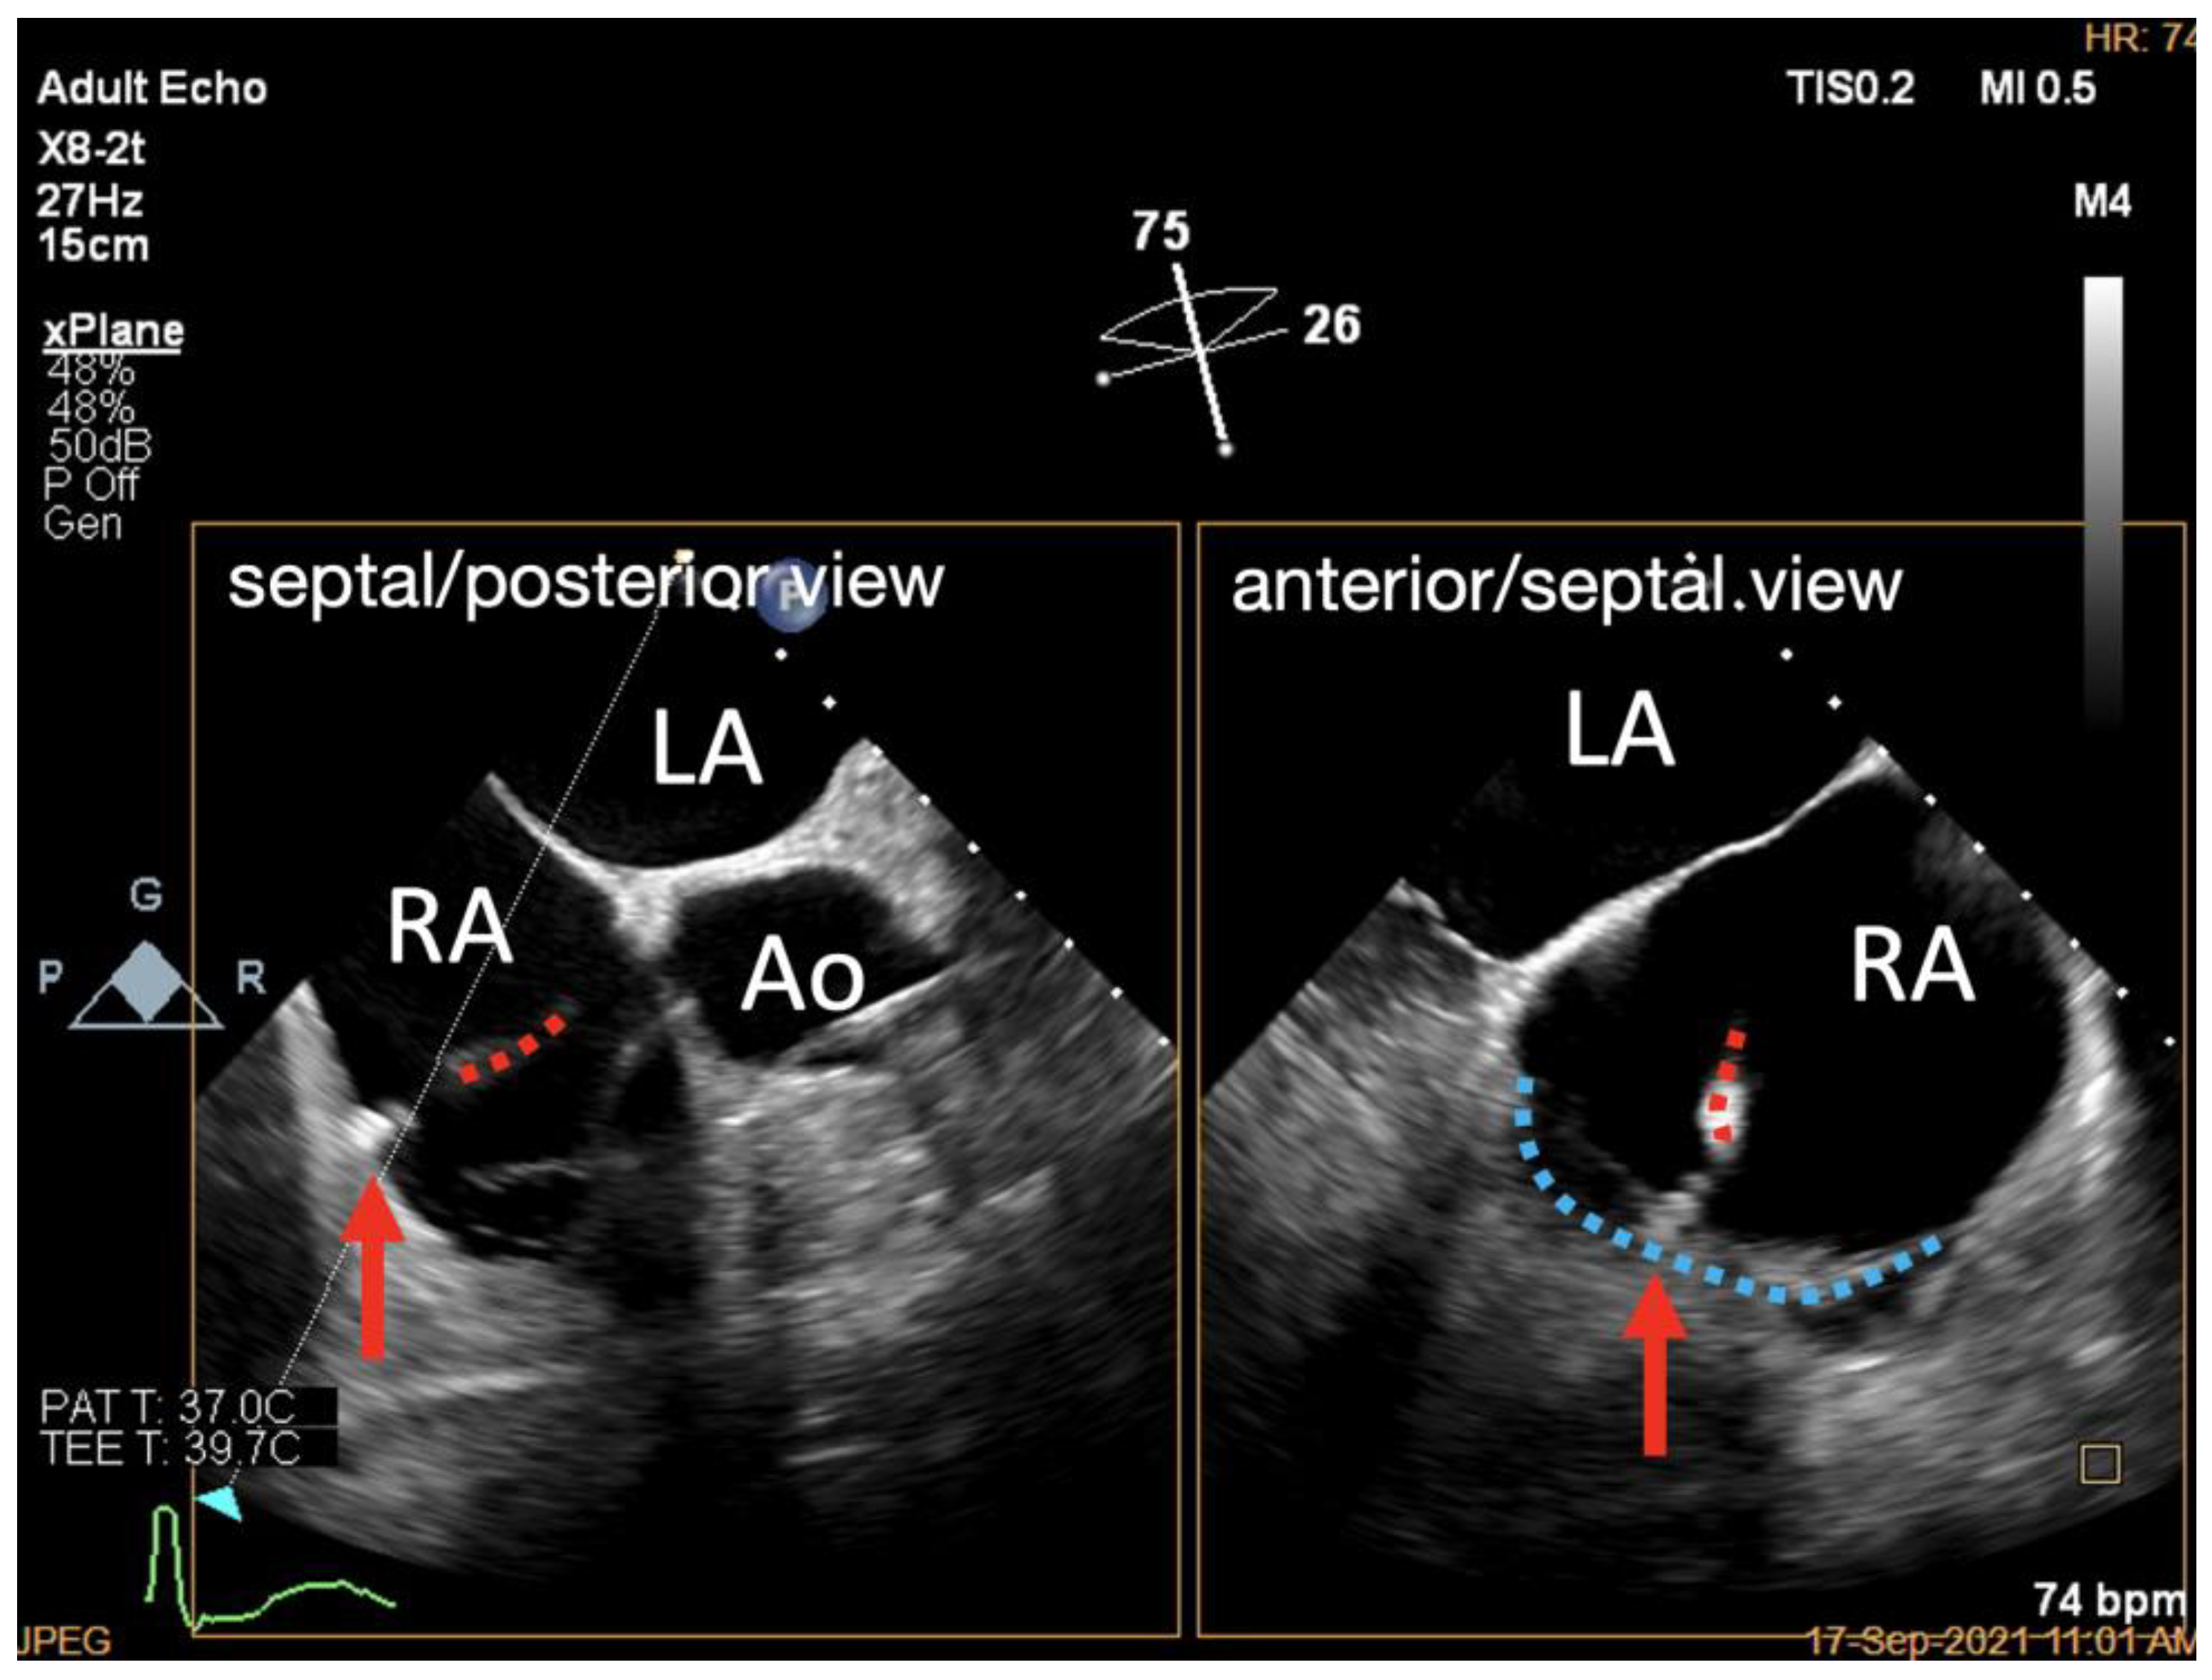

3.6. Assessment of Clutch Status

| Step 5. Assessment of clutch status | X-plane view with ME RV inflow–outflow view as the primary view | about 60° | Clip stability is preferably verified under 2D imaging due to its high resolution |

| 3D TV en face view | Any angle permitting acquisition of the whole TA volume would be acceptable |